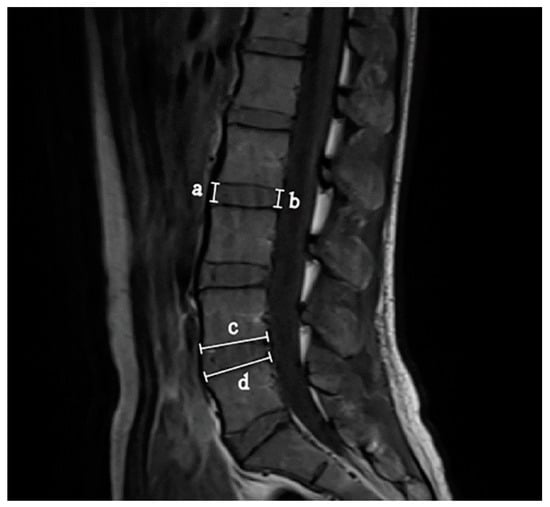

2.2.3. Disc Morphology Measurement